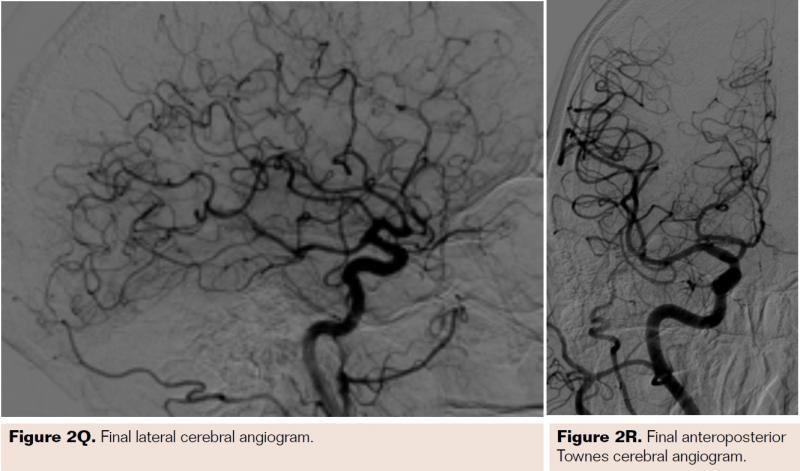

Pretreatment with dual-antiplatelet therapy (DAPT) was started 4 days prior to the procedure with aspirin and clopidogrel, with 600 mg loading dose of clopidogrel and 80 mg dose of atorvastatin the morning of the procedure. The right radial artery was accessed with a 6 Fr Terumo radial sheath, but intraarterial nitroglycerin was not administered due to a prior history of profound hypotension with sublingual nitroglycerin. Verapamil was withheld due to a systolic blood pressure of 130 mm Hg. Both right and left anterior oblique arch aortograms with a 5 Fr straight pigtail catheter demonstrated patency of the proximal great vessels, a type I aortic arch, and a calcified proximal right internal carotid artery (ICA) high-grade stenosis with patent right external carotid artery (ECA). The right common carotid artery (CCA) was selected with 5 Fr internal mammary (IM) diagnostic catheter that confirmed an 85% proximal right ICA stenosis. A soft-angled .035˝ Glidewire (Terumo) was advanced into the right ECA, exchanged out for an Amplatz .035˝ super-stiff wire (Boston Scientific), followed by removal of the diagnostic catheter, and radial sheath. A 6 Fr Shuttle sheath (Cook Medical) was delivered into the distal right CCA. After intracranial angiography, a NAV-6 Emboshield (Abbott Vascular) was deployed in the distal extracranial ICA, followed by predilation with a 4 x 30 mm Trek (Abbott Vascular), and deployment of a 7 x 30 mm Precise self-expanding stent (Cordis). Postdilation was performed with a 5 x 20 mm Maverick NC balloon (Boston Scientific), and then with a 6 x 20 mm Aviator balloon (Cordis) in order to then deliver the retrieval catheter. After repeat angiography confirmed an excellent result, the Shuttle was removed, and hemostasis achieved with TR band (Terumo) (Figures 2A-2R).